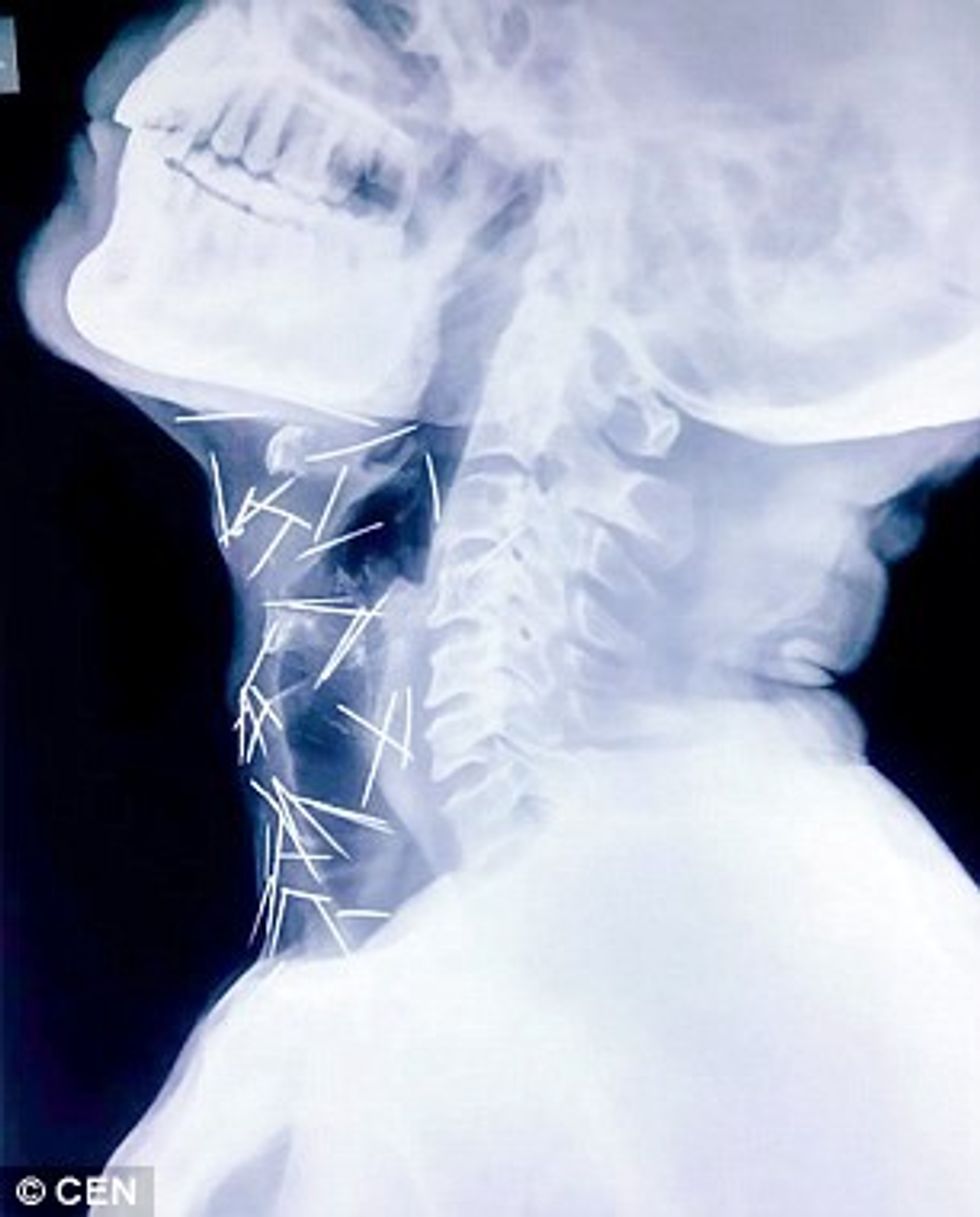

Mjekët gjetën 75 gjilpëra në duart, këmbët dhe qafën e pacientit (Foto)

Badrilal Meena nga Kota i Indisë, kishte shkuar te mjeku me dhimbje të mëdha në gishtin e madh të këmbës, por është befasuar kur i janë gjetur 75 gjilpëra në pjesë të ndryshme të trupit.

Pacienti 56-vjeçar, nuk di si janë futur pjesët metalike, ndërsa mjekët dyshojnë se ai i ka përpirë kohë pas kohe dhe i janë shpërndarë më pas, transmeton Telegrafi.

Fillimisht, atij ia kanë zbuluar në shputën e këmbës, pastaj është vendosur t’i bëhet një fotografim komplet me rreze X, mirëpo nuk është zbuluar prejardhja tyre.

Megjithëse është shtrirë në spital, ende nuk është intervenuar që t’i hiqen 40 gjilpëra nga fyti, 25 nga këmbët dhe dhjetë të tjera nga duart.